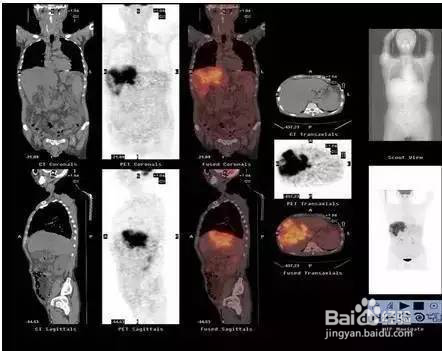

作为核医学的代表,PET/CT 是将PET与CT技术融为一体,通过一次显像,可以获得全身各个部位的断层图像,具有特异及定位精确等特点。通过PET/CT,最小可以诊断出3-5毫米大小的肿瘤,可一目了然地了解全身状况,达到早期发现病灶、诊断疾病的目的。

癌细胞会无限生长、转化和转移,能够无限增殖并破坏正常的细胞组织。其赖以生存的能量来源是葡萄糖,癌细胞吸收的葡萄糖是正常细胞的3-8倍,所以注射和葡萄糖成分接近的FDG药剂后,FDG药剂会被吸收集中到癌的患处。从药剂集中处放出大量的放射线,而从捕捉到的影像上可以由FDG的分布状态找出癌的病变处。目前为止,X线检查只能发现37.5px以上的癌瘤,核磁(MRI)及CT检查也仅能发现25px以上的癌瘤,此时 癌症已达中期或末期,无法达到早期发现的目的。

PET-CT是目前世界上能检测最小的癌细胞的最先进的机器, 对于实施检测人员以及读片人员都有较高要求。一般来说,PET检查能相对准确的发现25px左右的癌细胞。现在世界临床PET-CT可以检查出的最小肿瘤大小为2mm,此时癌瘤处于早初期,治疗后痊愈的可能性很大。